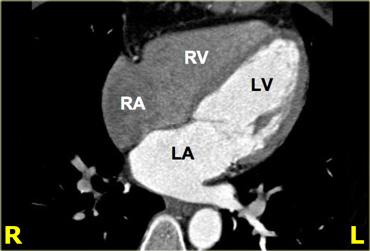

Các lát cắt ngang, như những lát cắt được hiển thị ở bên trái, hữu ích cho việc đánh giá tổng thể hình thái của tim và mối liên quan của nó với màng ngoài tim.

Mặt cắt 4 buồng